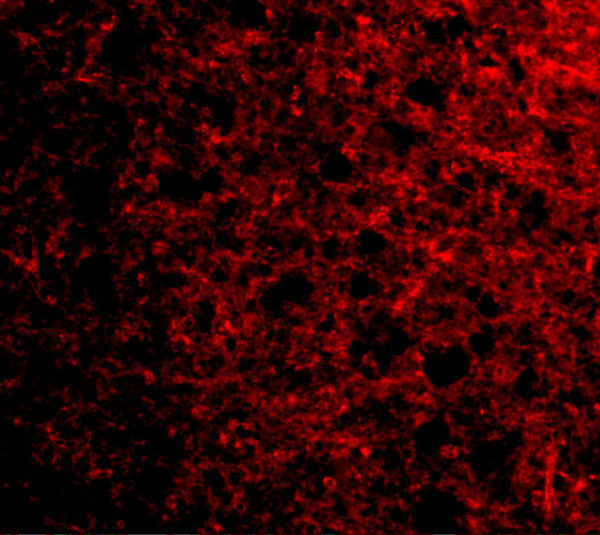

IHC (Immunohiostchemistry)

(Immunohistochemical analysis of paraffin-embedded human breast carcinoma tissue using Stathmin 1(Phospho-Ser38) Antibody(left) or the same antibody preincubated with blocking peptide(right).)